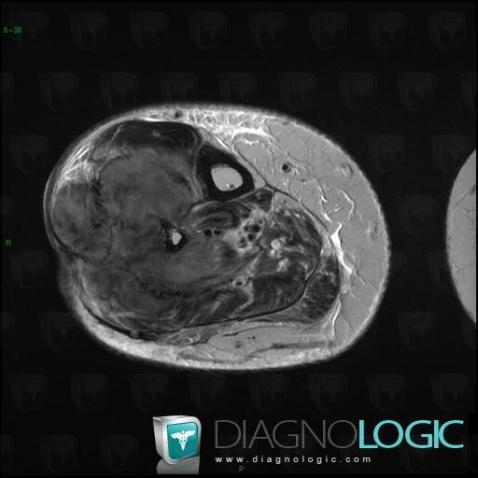

Osteosarcoma, Muscles - Leg, Other soft tissues/nerves - Leg, MRI

Here is the specific information in the key image above:

- Diagnosis Osteosarcoma, Location(s) Muscles - Leg, with gamuts Soft tissue mass with osteolysis, Hypointense T2 WI soft tissue lesionOther soft tissues/nerves - Leg, with gamuts Hypointense T2 WI soft tissue lesion